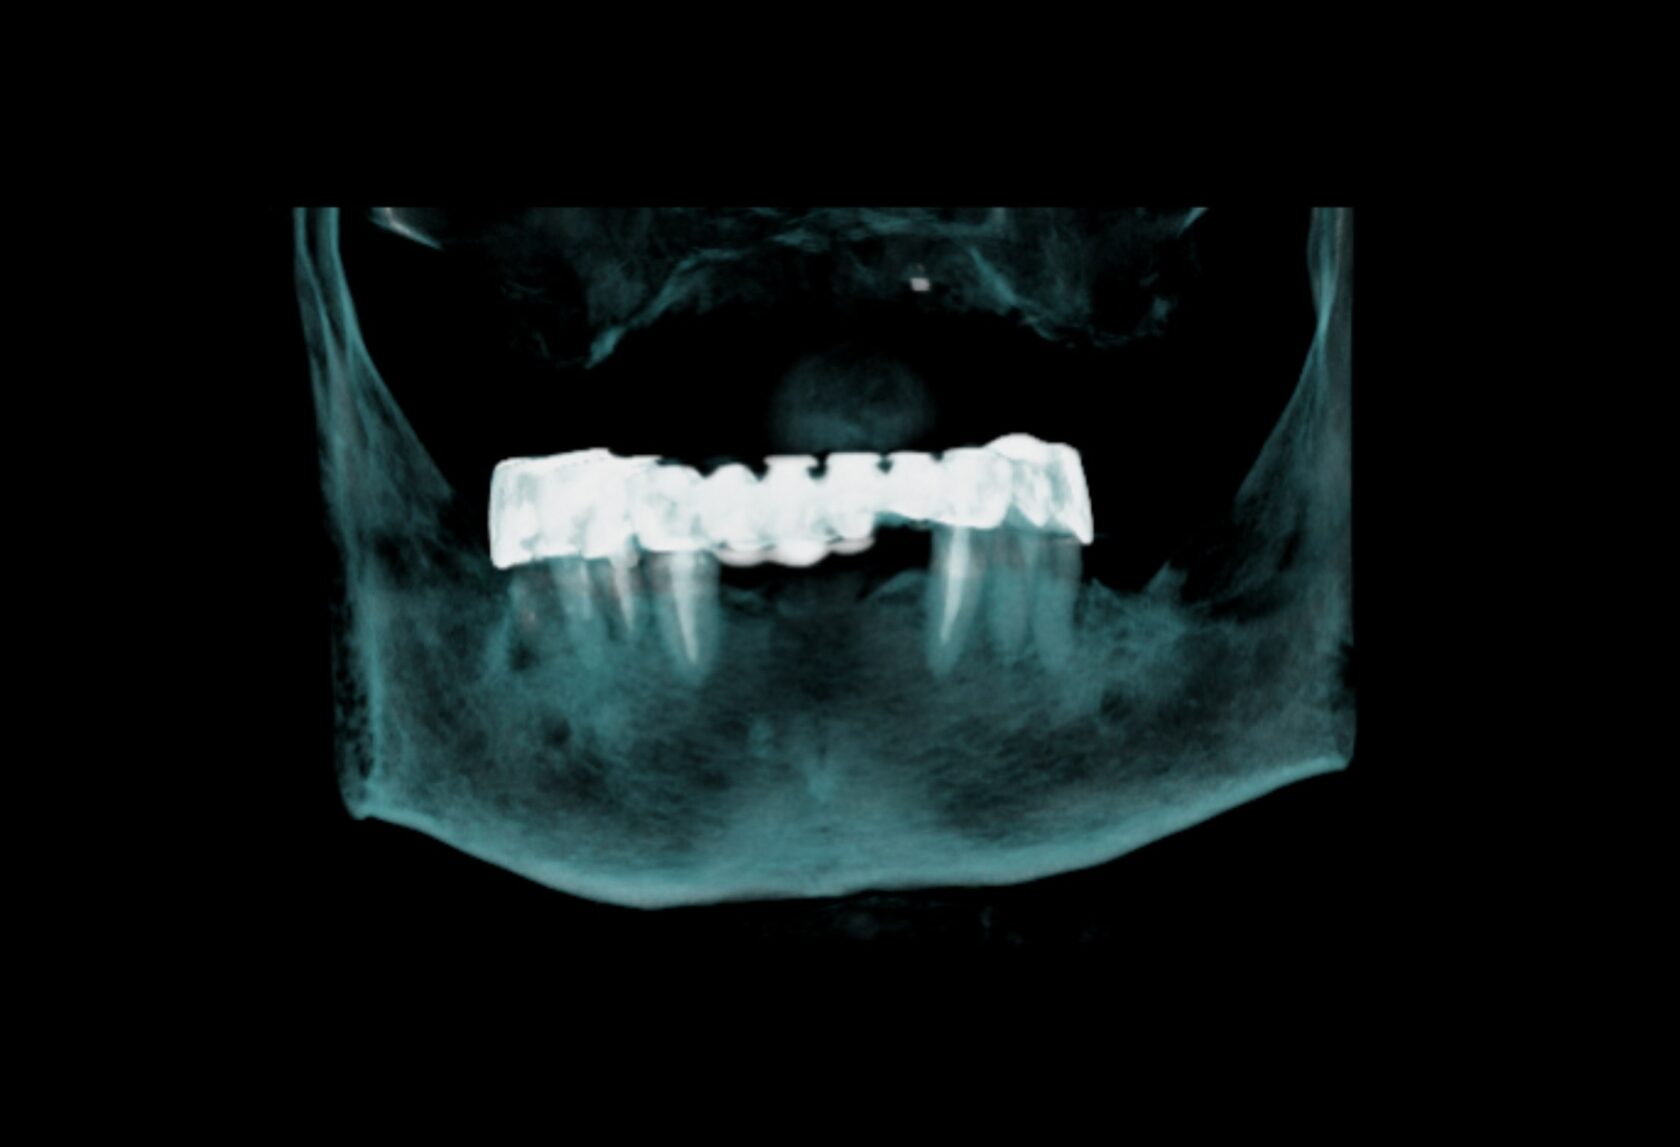

Планирование имплантации, хирургических шаблонов и оценка ретенированных клыков.

Высокоточная эндодонтическая оценка, планирование одиночных имплантатов.